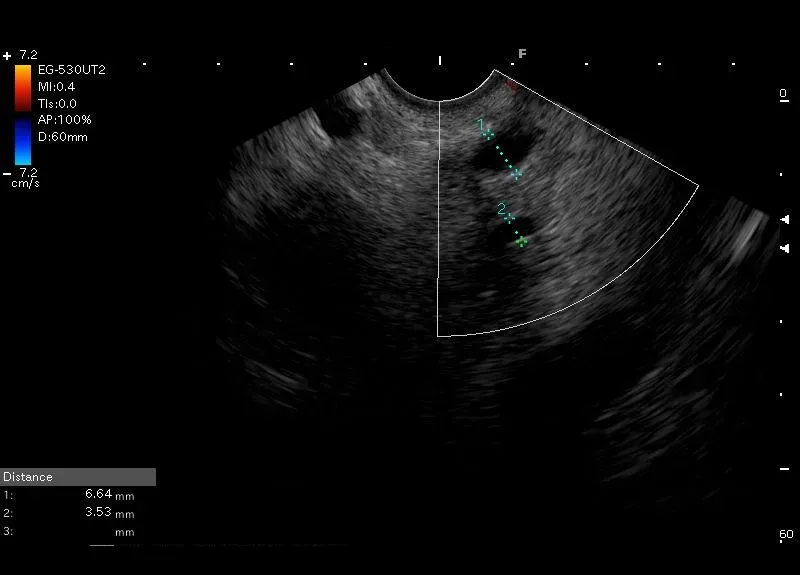

Położony bliżej głowicy EUS, szerszy, o grubszych ściankach  przewód żółciowy wspólny i położony  poniżej węższy  przewód Wirsunga.

Przewody widziane w głowie trzustki, przy głowicy umieszczonej w okolicy brodawki Vatera